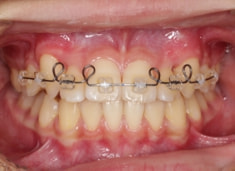

(難症例のため、小児期の矯正を2段階に設定しました)

治療開始時

検査時のレントゲン分析では、上下顎の関係は、上顎の劣成長があり下顎前突傾向という値がでておりましたが、前歯ジャンプ後はフェイスマスクの効果もあり、上下顎の関係は正常化しています。

上顎が若干優位になっていますので、今後の下顎の成長のための貯金になっているくらいです。